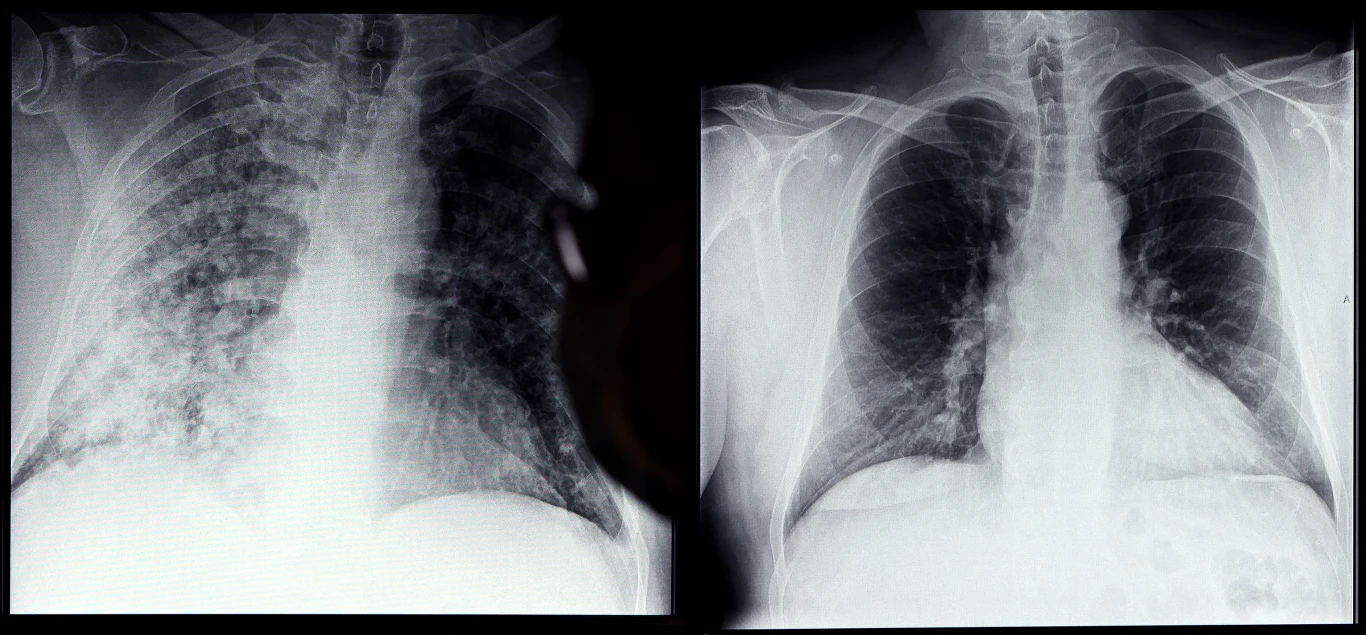

Badanie: COVID-19 może powodować niemal niewykrywalne zmiany w płucach

U pacjentów, którzy przechorowali COVID-19, wykryto mikroskopijne uszkodzenia płuc, których nie było widać przy rutynowych testach - wynika z badań brytyjskich naukowców. Anomalie mogą powodować duszności na długo po zakażeniu.

Zobacz też: Nowe przypadki koronawirusa. Dane Ministerstwa Zdrowia z 29 stycznia- To pierwsze badanie skupiające się na osobach, które cierpią na duszność po przebytym COVID-19. Badania tomograficzne nie wykazywały jednak żadnych nieprawidłowości. Sugeruje to, że wirus powoduje anomalie w mikrostrukturze płuc lub unaczynieniu płucnym - mówiła cytowana przez "The Guardian" współautorka badania dr Emily Fraser, konsultantka w szpitalach uniwersyteckich w Oksfordzie.